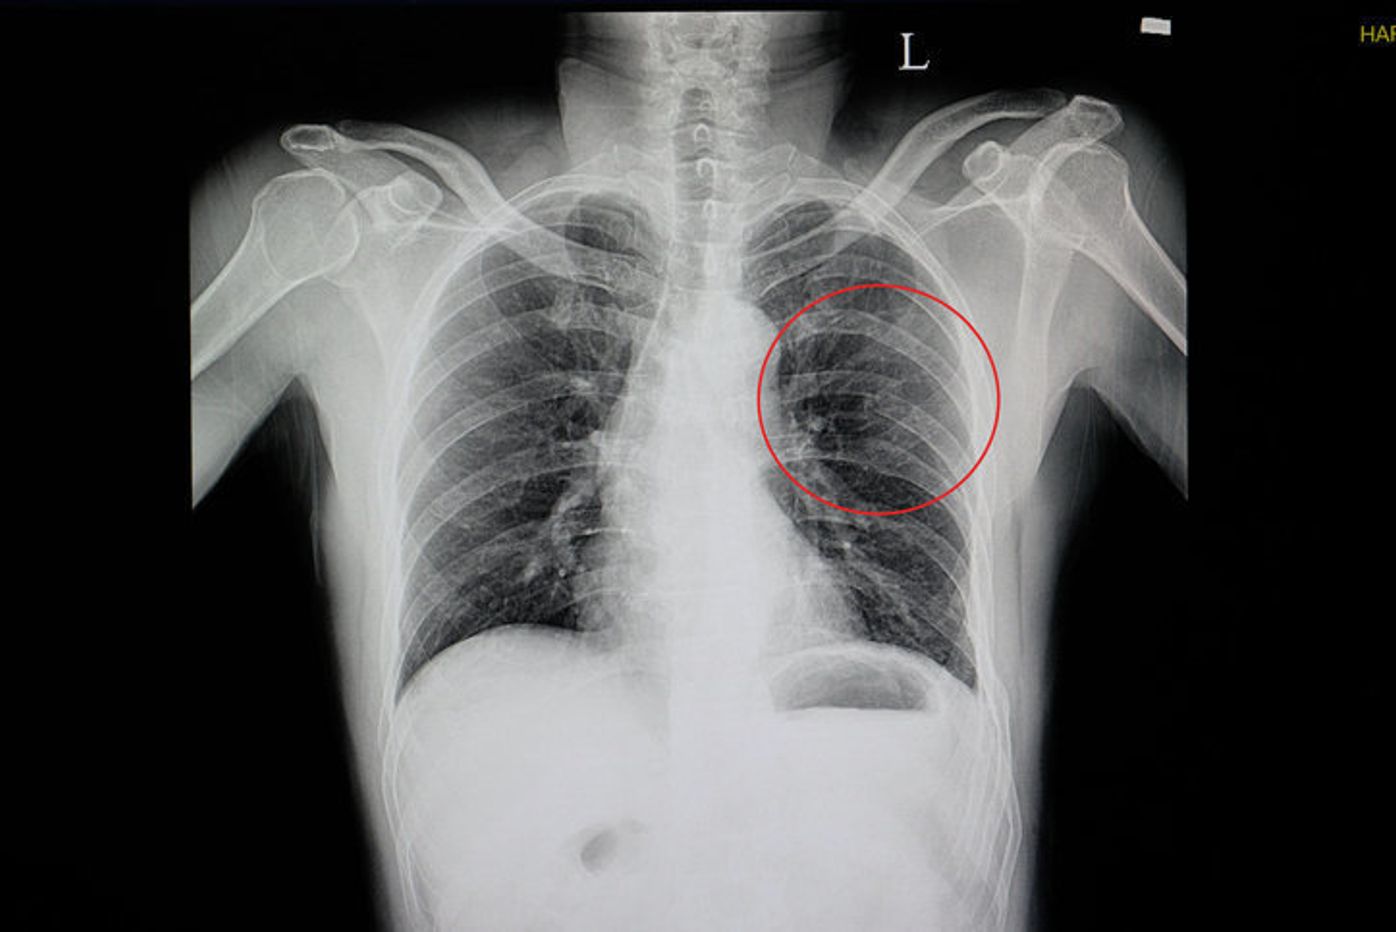

また、肋骨骨折の場合にはレントゲンにもうつりにくいです。 そのため、軽度だと考えて放置してしまうと1週間、2週間経っても治らないことがあります。 その場合には骨折の可能性もありますので、再度病院を受診しましょう。 まとめ肋骨骨折とは?症状・全治(完治)・痛み・リハビリなどを解説 肋骨骨折の全治(完治するまでの期間) 肋骨骨折の全治は、症状によって差はあります。軽症の肋骨骨折で軽いヒビが入った程度のであれば、 完治まで2~3週間程度ということが多い です。 肋骨骨折の完治にかかる期間は? 骨折の程度によって、肋骨骨折の完治にどのくらいかかるかは異なります。 また、加齢と共に少しずつ骨の生成能力が減少していくため、 高齢の人ほど治療が長びく傾向があります 。 小さなひびが入った程度であれば、2、3週間ほど安静にすれば回復しますが、完治までには2カ月ぐらいかかると言われています。 スポーツ選手の

肋骨骨折 で手術が必要となることはまれですので、大病院である必要はなく、クリニックで十分な対応が可能です。 肋骨骨折 の診断は診察とレントゲンで行います。 場合によってはエコーやCTを補助的に使用しますが、初期の小さな骨折は画像検査に写りにくいことが多いです。 CTであれば大抵の骨折はわかるものの、それほどまで小さな骨折であれば治療法はどんな骨折か 肋骨は胸部に左右12本ずつ存在し、鳥かごのようになっていて、肺や心臓を包むように保護しています。 通常、転倒など 打撲 した時に起こりますが、けががなくとも長い間咳が続いたり、ゴルフスイングを繰り返すだけで骨折することも 肋骨骨折の合併症(肋骨骨折を甘く見ないで! 18年12月3日 / 最終更新日時 18年12月3日 佐野古東整形外科 体幹の疾患 「ろっ骨にひびが入った」とか、「あばらが折れた」など、 日常でよく聞く骨折のことですが、